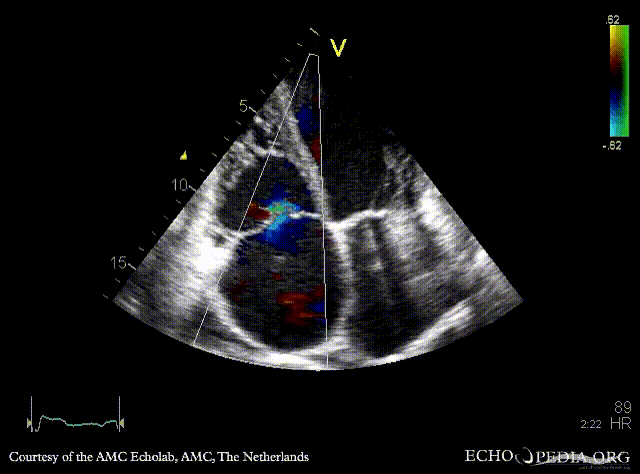

Severe prolaps of PMVL

PLAX: prolaps of PMVL, huge amount of pleural effusion PLAX: Color Doppler, severe mitral regurgitation, excentric jet